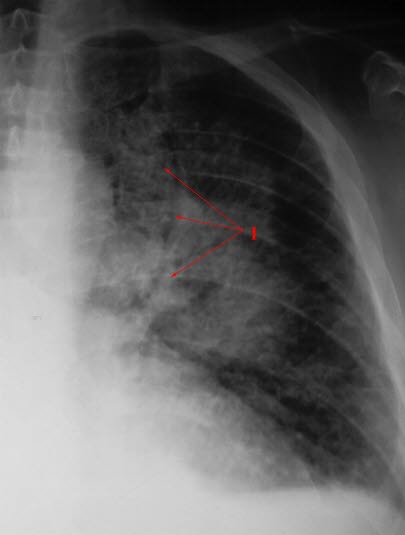

Utbredt fortetning i sentrale deler av lungen på grunn av væskeutsiving i lungene (1)